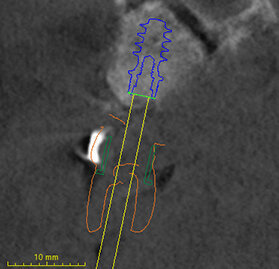

Nei casi di atrofie marcate, è fondamentale ricostruire l’osso mancante ma anche poter dare all’arcata una forma ideale. In questo caso clinico la paziente si presenta alla mia osservazione con una marcata atrofia del mascellare superiore (Fig. 1). La valutazione clinica è stata effettuata con esami radiografici di routine, OPM ed endorali, ma soprattutto con una Cone Beam TC. Da alcuni anni infatti, effettuo tutte le valutazioni diagnostiche in ambiente CAD con un software di chirurgia computer guidata che consente di valutare l’osso residuo in relazione al posizionamento tridimensionale dell’impianto protesicamente guidato.

L’approccio è quello di duplicare la protesi mobile utilizzata quotidianamente dalla paziente per renderla, attraverso punti di repere radiopachi, protesi radiologica. La paziente eseguirà la Cone Beam con la protesi radiologica e grazie alla presenza dei punti di repere radiopachi si potrà fare il matching tra i dati DICOM e la protesi della paziente (Figg. 2-4). Durante questa prima valutazione risulta evidente l’assenza di osso attorno agli impianti. La marcata perdita ossea è prevalentemente orizzontale e si estende in senso antero-posteriore su tutta l’arcata mascellare. Nella zona degli incisivi il posizionamento protesicamente guidato non è possibile a causa dell’assenza orizzontale dell’osso. Nelle zone posteriori inoltre si evidenziano i prolassi dei seni mascellari che riducono ulteriormente la disponibilità ossea. Di fronte a un quadro clinico così complesso si rende necessaria una scelta oculata della tecnica ricostruttiva adeguata.

Stabilita la tecnica rigenerativa è necessario fare delle valutazioni sul periodo post operatorio e quindi sul tipo di protesi provvisoria da far indossare alla paziente. Escludendo tutte le tipologie di protesi mobili per almeno sei mesi (compresa quindi una protesi sostenuta da un impianto posizionato nel palato), sempre con l’ausilio del software di chirurgia guidata ho quindi ipotizzato l’inserimento di due impianti nella zona della tuberosità (Fig. 5). Con l’ausilio della dima chirurgica sono stati inseriti tre impianti, due nelle tuberosità mascellari e uno nel palato (Fig. 6). Sui tre impianti è stato progettato insieme ai tecnici un dispositivo in metallo che potesse sostenere dei denti fissi non rimovibili (Fig. 7). Il risultato ottenuto è stato eccellente perché la paziente ha portato una protesi fissa fin dal giorno dell’intervento per tutto il periodo di guarigione, di circa nove mesi. La progettazione della ricostruzione ossea è stata quindi fatta in maniera Protesicamente Guidata, sono stati posizionati gli impianti virtuali e poi valutata l’entità della rigenerazione necessaria.

Inoltre da questa nuova ceratura dobbiamo ricavare una protesi radiografica con i punti di repere radiopachi che ci servirà per fare il matching con i nuovi file DICOM dell’osso rigenerato (Figg. 35, 36). Fatte le opportune verifiche nel software di chirurgia guidata, si pianifica l’intervento di posizionamento implantare (Figg. 37-40). Si programma lo stesso giorno della chirurgia anche il carico immediato degli impianti; decisione supportata dalla verifica istologica dell’osso rigenerato che dovrà comunque essere confermata il giorno del posizionamento implantare durante il quale si misurerà il torque di inserimento degli impianti e la stabilità primaria con il sistema OSSTELL mentor (Integration Diagnostics) che sfrutta l’analisi della frequenza di risonanza.

Grazie al flusso digitale, possiamo inserie nel software anche il file STL del provvisorio pre-chirurgico preparato e quindi progettare il provvisorio immediato (Fig. 41). La pianificazione degli impianti a questo punto viene effettuata in modo protesicamente guidato ed è facile posizionare correttamente l’impianto e verificarlo nelle cross del software. Si progetta e si disegna quindi la dima chirurgica (Fig. 42). Il giorno dell’intervento abbiamo già tutto pronto e la paziente presenta uno stato di salute dei tessuti ottimale grazie anche al fatto che ha potuto portare per tutto il periodo una protesi fissa.